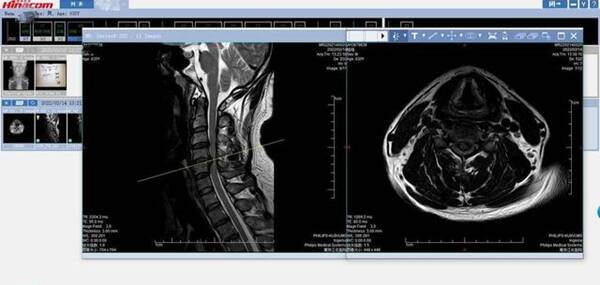

李濤院長在仔細(xì)詢問小陸的病情后,考慮為頸椎間盤突出壓迫神經(jīng)后出現(xiàn)的一系列癥狀,建議行頸椎MRI檢查進(jìn)一步明確診斷。MRI的檢查結(jié)果令李濤院長感到很吃驚,年輕輕輕的小陸頸椎間盤嚴(yán)重突出,壓迫脊髓,甚至已經(jīng)出現(xiàn)了脊髓部分變性。這就意味著,小陸急需手術(shù)解除壓迫,恢復(fù)神經(jīng)功能。

結(jié)合各項(xiàng)檢查結(jié)果,李濤院長為小陸量身制定手術(shù)方案,“頸前路椎體次全切除術(shù)+3D打印人工椎體植入鈦板重建術(shù)+椎間盤切除術(shù)”。僅用時(shí)1小時(shí),就將問題完全解決。術(shù)后當(dāng)天,小陸就覺得自己的疼痛徹底緩解了,感受到了這些天來前所未有的舒適。術(shù)后第二天,就可自行下地活動,復(fù)查X線提示為小陸定制的3D打印人工椎體與其完美適配。